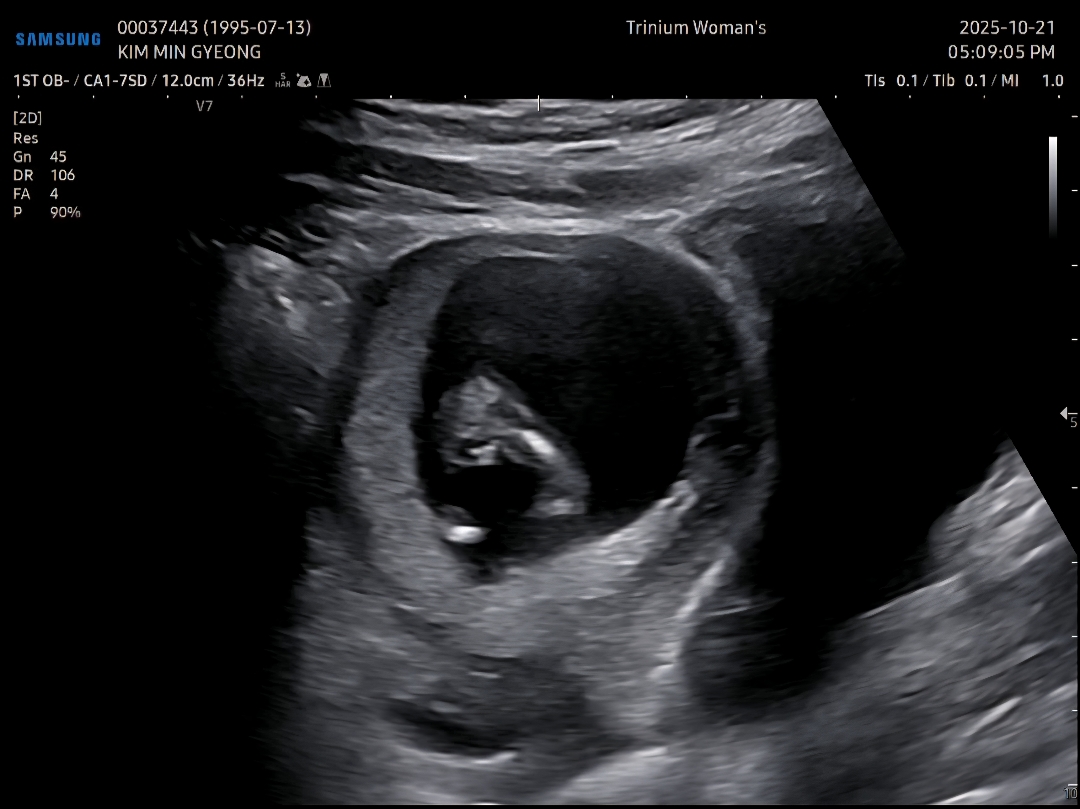

11주 6일 1차 기형아 검사 다녀왔어요

애기크기 12주 4일로 잘 자라고 있고 통합검사 선택해서 목둘대 투명대 쟀는데 1.3mm로 정상이래요 ㅎㅎ 근데 의사선생님께서 애기 다리사이를 보시더니 아들같으시다고 그러시는거에요?ㅋㅋㅋ큐ㅠㅠㅠㅠ 집와서 초음파 영상보니까 다리사이에 선명한 동그라미두개.... 원래 12주에 이렇게 선명하게 보이나요??? ㅋㅋㅋㅋㅋㅋ 이정도로 보이면 아들확정이겠죠???😂